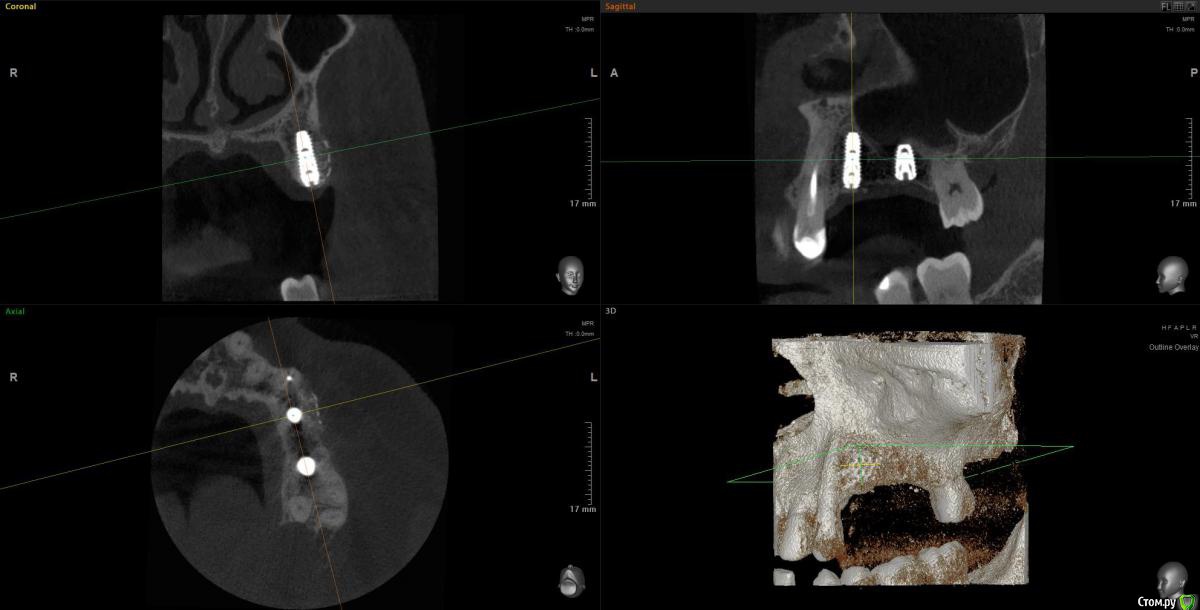

Snow Doc Опубликовано 1 сентября, 2020 Поделиться Опубликовано 1 сентября, 2020 Кажется взяли кусок титановой сетки и прикрутили заглушкой к болту. А мы тут про сиартбилдеры, спейсеры... И так работает у кого-то) Ссылка на комментарий

АнтонТЛТ Опубликовано 1 сентября, 2020 Поделиться Опубликовано 1 сентября, 2020 Кажется взяли кусок титановой сетки и прикрутили заглушкой к болту. А мы тут про сиартбилдеры, спейсеры... И так работает у кого-то)А что спейсер на кт уже не видно?)) Ссылка на комментарий

Марья Моревна Опубликовано 1 сентября, 2020 Поделиться Опубликовано 1 сентября, 2020 А что спейсер на кт уже не видно?)) Я вижу и на фото.Антон, а Ваша клиника случайно не "Леонардо да Винчи" называется? )) Ссылка на комментарий

Женька Опубликовано 2 сентября, 2020 Поделиться Опубликовано 2 сентября, 2020 Кажется взяли кусок титановой сетки и прикрутили заглушкой к болту. При таком варианте не получится же винт утопить на 1-1.5мм? Ссылка на комментарий

Snow Doc Опубликовано 4 сентября, 2020 Поделиться Опубликовано 4 сентября, 2020 А что спейсер на кт уже не видно?))Сейчас видно. А тогда было поздно вечером и не видно Ссылка на комментарий